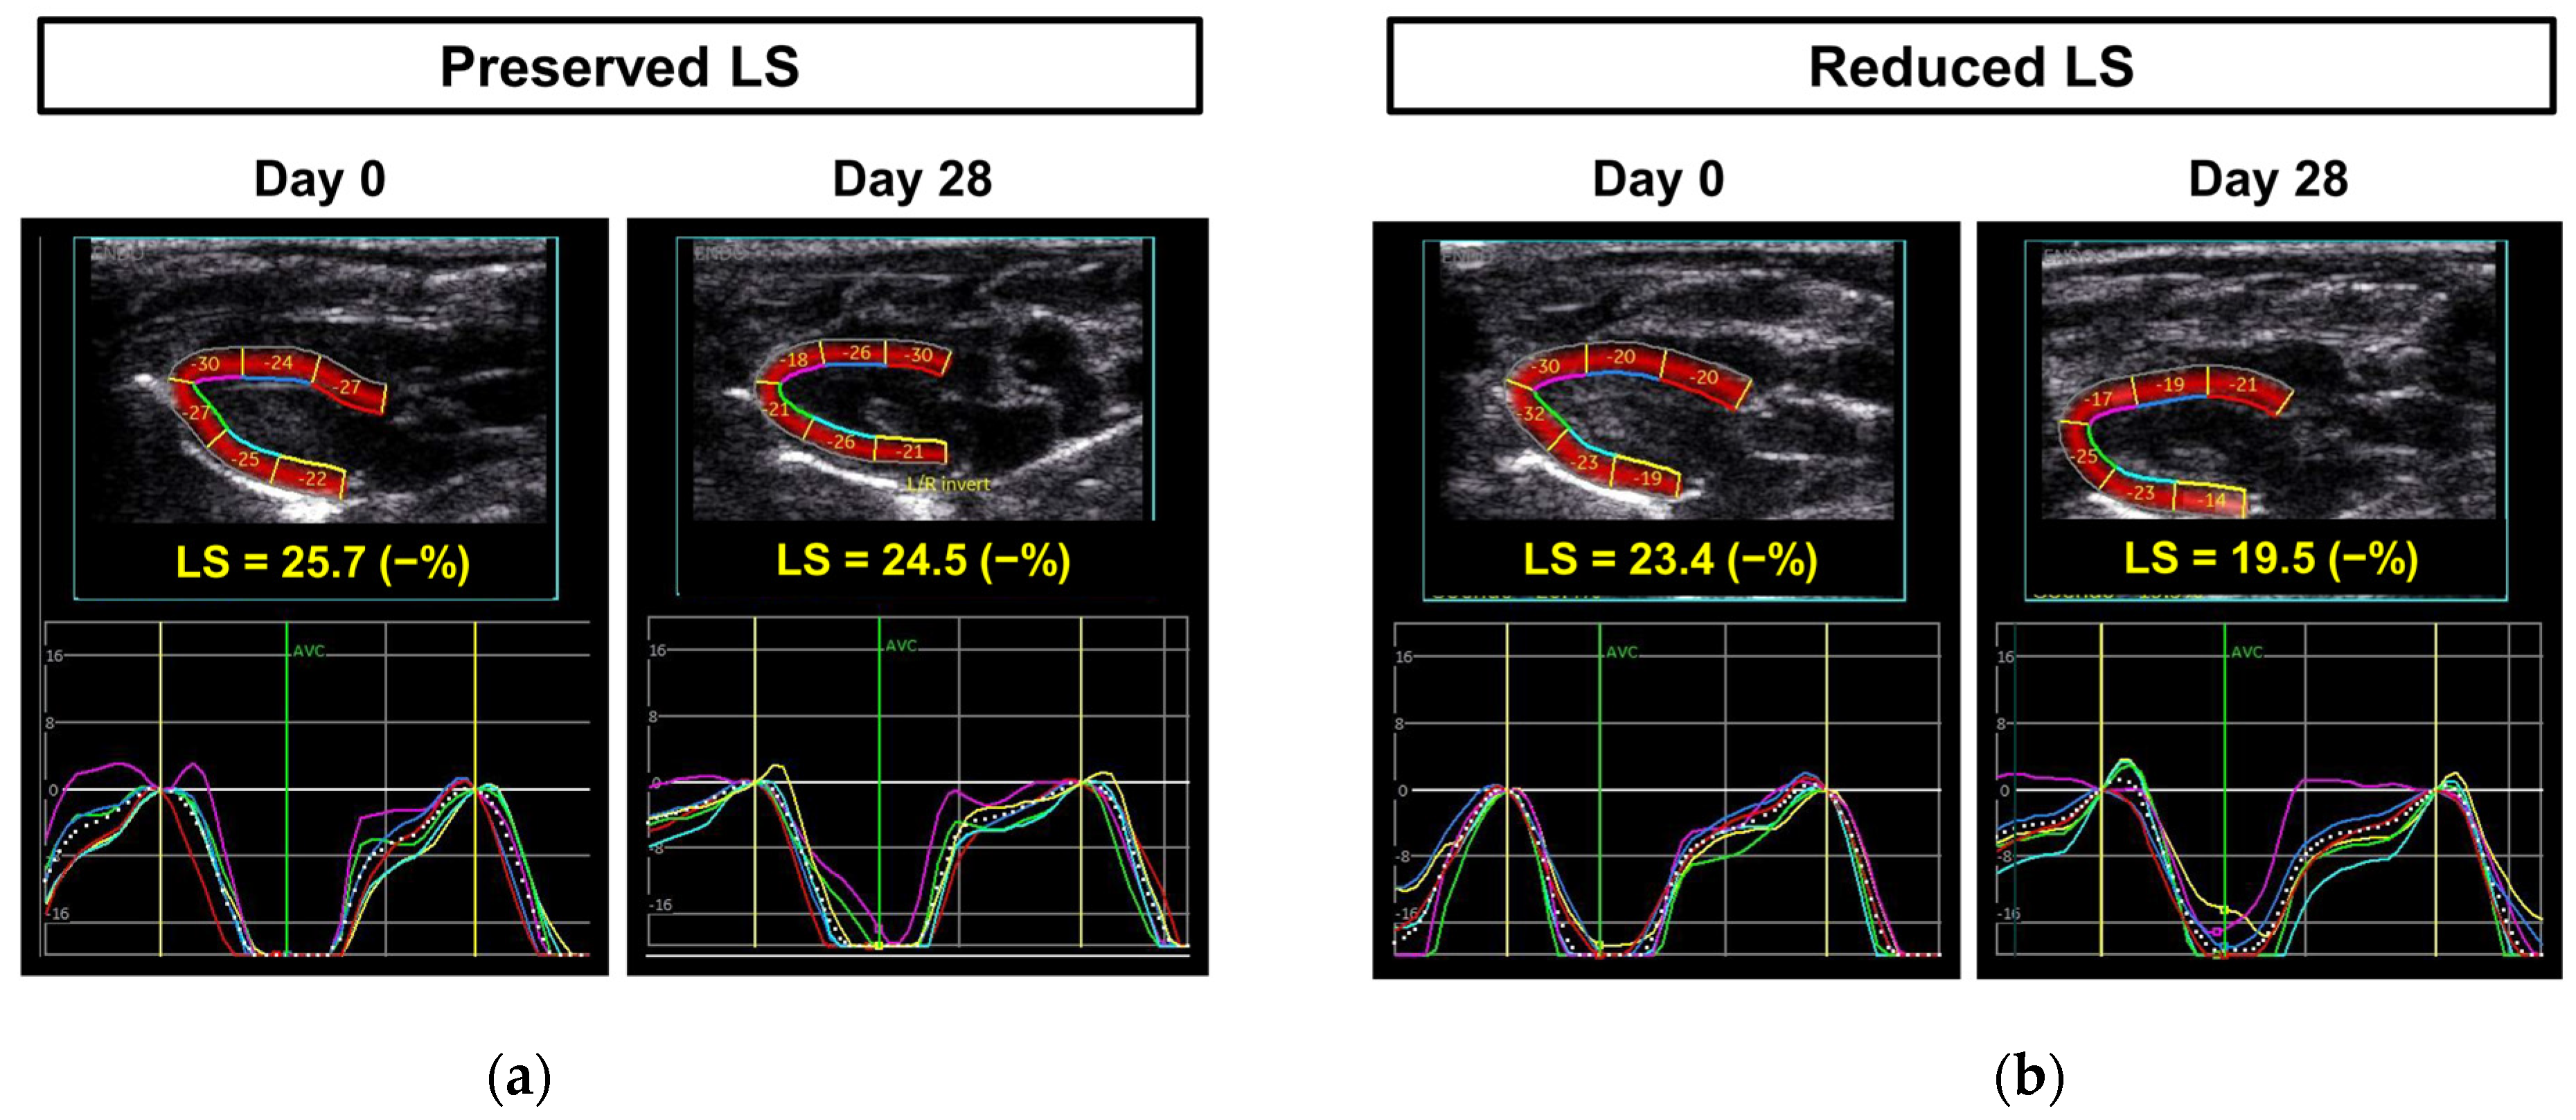

| LS, −% | 23.8 ± 1.9 | 23.7 ± 1.5 | 0.883 |

| LS, −% | 24.7 ± 1.1 | 20.7 ± 1.2 | <0.001 |

| %Change in LS † | 4.2 ± 11.0 | −11.5 ± 7.7 | <0.001 |